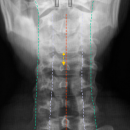

Dens (Spezialaufnahme)

CAVE

- 1) Exakte Aufnahmetechnik? - Projektion korrekt?

- 2) Atlantoaxialer Übergang: Distanz Dens-Massa lateralis ? (Distanz 3-5mm = V.a. parteielle Ruptur des Lig transversum; Distanz > 5mm = V.a. komplette Ruptur des Lig. transversum)

- 3) Konturlinien überprüft: Laterale Konturlinien, Dornfortsatzlinien

Beurteilung von

- Atlas

- Axis mit Dens axis

- Atlantoaxialgelenk